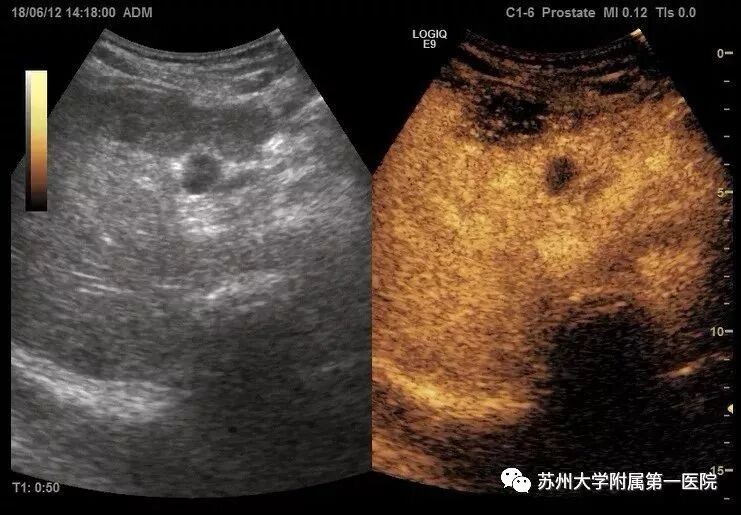

病例2

情况:女,30岁,体检发现甲状腺结节

结节边缘模糊,似呈毛刺样,二维超声提示恶性可能大,建议FNA(细针穿刺抽吸细胞学检查)。患者心理压力较大。

灰阶图像

超声造影图像

选择超声造影原因:超声造影显示结节始终无明显增强,考虑为结节性甲状腺肿结节出血后皱缩所致。为良性病变,避免了无效的穿刺,极大缓解了病人心理压力。